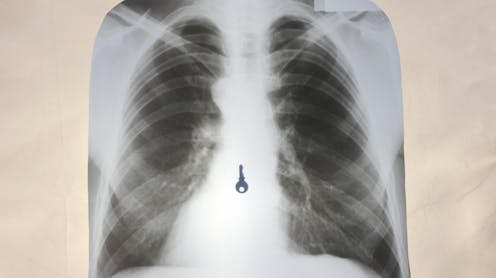

Although most of the time, ingested foreign bodies pass naturally, around 10-20% of cases require endoscopic retrieval (a camera and small tools entering your mouth to get to your stomach) – and 1% require emergency surgery. In adults, the most commonly ingested foreign bodies are fish or chicken bones. In children, it’s coins, button batteries and toy parts.

Small items, such as earrings, aren’t too difficult for the body to pass if swallowed accidentally or on purpose. This is because the oesophagus, which carries food to the stomach, is up to 3cm in diameter.

But if objects are too large and get stuck in the oesophagus, they can tear and perforate it. A tear to the oesophagus requires immediate medical intervention – without emergency care, this tear has a mortality rate of up to 40%.

The stomach, a J-shaped sac, has a much larger diameter than the oesophagus. It then connects to the small intestines and subsequently the large intestines. But because of the stomach’s unique shape and the way it tightly narrows as it joins the small intestines, objects can easily get lodged in this join.

In one case study, doctors in Iran removed more than 450 metallic items from a man’s stomach – including screws, keys, nuts and other metal parts. These objects weren’t able to pass naturally due to the narrowing of the digestive tract – subsequently building up in the stomach, leading to abdominal pains and digestive issues in the patient that required immediate surgery.